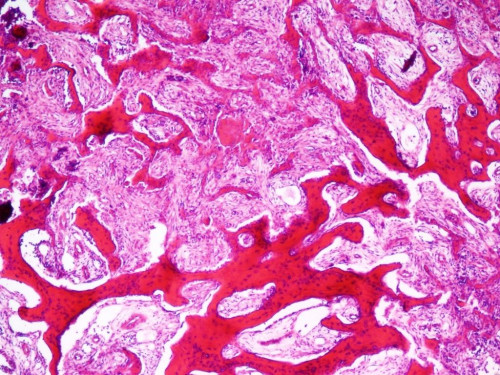

11-jähriges Mädchen. Sie klagt schon seit längerem über Schmerzen im linken Fuß, die insbesondere nachts auftreten. Ihre Mutter tut es anfangs noch als Wachstumsschub ab. Als ihre Beschwerden nach ein paar Wochen aber immer noch nicht verschwunden sondern sogar eher stärker geworden sind, wird die Mutter misstrauisch. Sie bringt ihre Tochter zum Kinderarzt, der eine Bildgebung veranlasst.